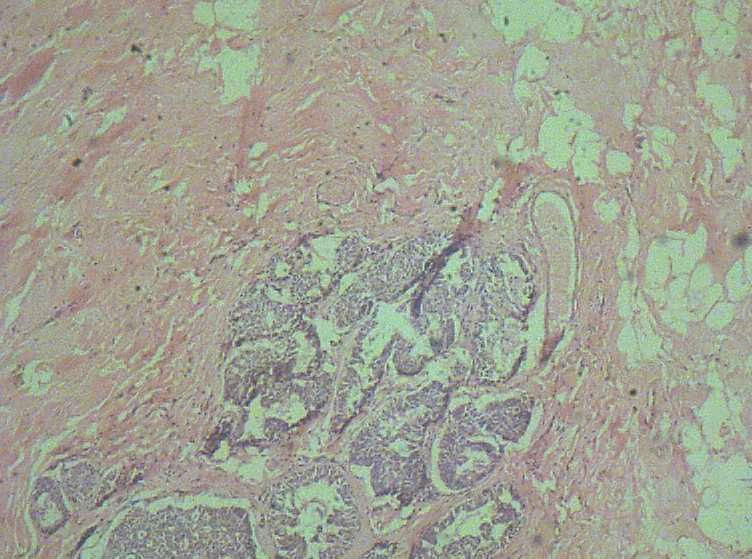

B3774乳腺积乳性包块?

女41岁,左腺包块。肉眼:不整形囊壁样组织,大小2*1.6*0.3CM,壁厚0.1—0.3,未触及结节,未见出血及坏死。

标签:乳腺纤维囊性增生症

似乎有导管扩张、慢性炎细胞浸润、大汗腺化生、普通型导管增生等病变,没有看到囊壁内衬上皮或囊壁结构。